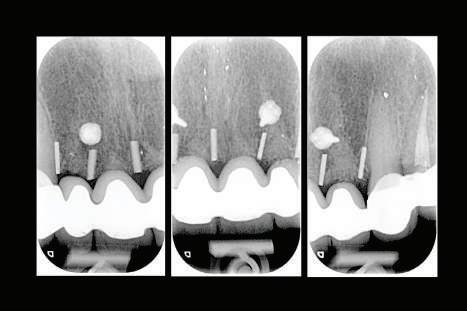

EXTINDEREA PROTOCOALELOR DE TRATAMENT

Protocoalele de tratament au fost dezvoltate într-un mod ce a facilitat confortul şi controversa. De exemplu, în trecut, protocolul standard prevedea permiterea integrării implantului, cu menţinerea sa neîncărcată pentru 6 luni la maxilar şi 3 luni la mandibulă ca timp minim de vindecare. În prezent industria asistă la protocoale care permit încărcarea la 3 săptămâni şi, desigur imediat în momentul inserării implantului.

Protocoalele de încărcare au fost scurtate, în mare parte datorită tratamentelor de suprafaţă îmbunătăţite. Microsuprafeţele care promovează integrarea rapidă sunt responsabile pentru duratele mai scurte de integrare. Geometria implanturilor a favorizat stabilitatea sporită la inserţie pentru protocoalele cu încărcare imediată.

Dacă însă implanturile sunt plasate prea vestibular sau prea superficial, componentele nu permit un design adecvat al bontului, pentru că plasarea marginii este limitată iar conturul facial şi proximal poate fi compromis (fig. 1, 2).

în susţinerea esteticii este limitat de procesul de planificare a tratamentului pentru restaurarea finală (fig. 3-5).